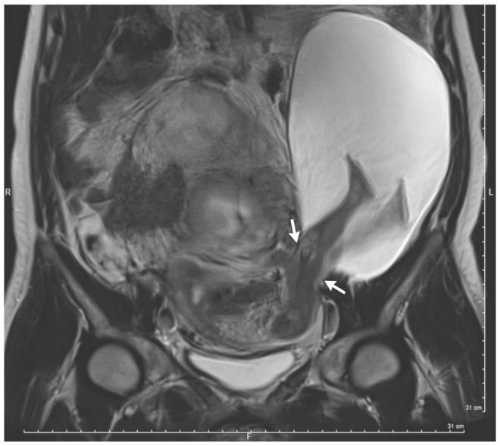

Đến tuần thứ 30, hình siêu âm cho thấy vết rách đã lớn hơn và thai nhi ngày càng ra ngoài tử cung. Tình hình nghiêm trọng buộc các bác sĩ phải ngay lập tức tiến hành mổ bắt con cho sản phụ. May mắn, em bé chào đời an toàn dù chỉ nặng 1,4 kg. 6 tháng sau ca sinh nở, hai mẹ con đều khỏe mạnh.